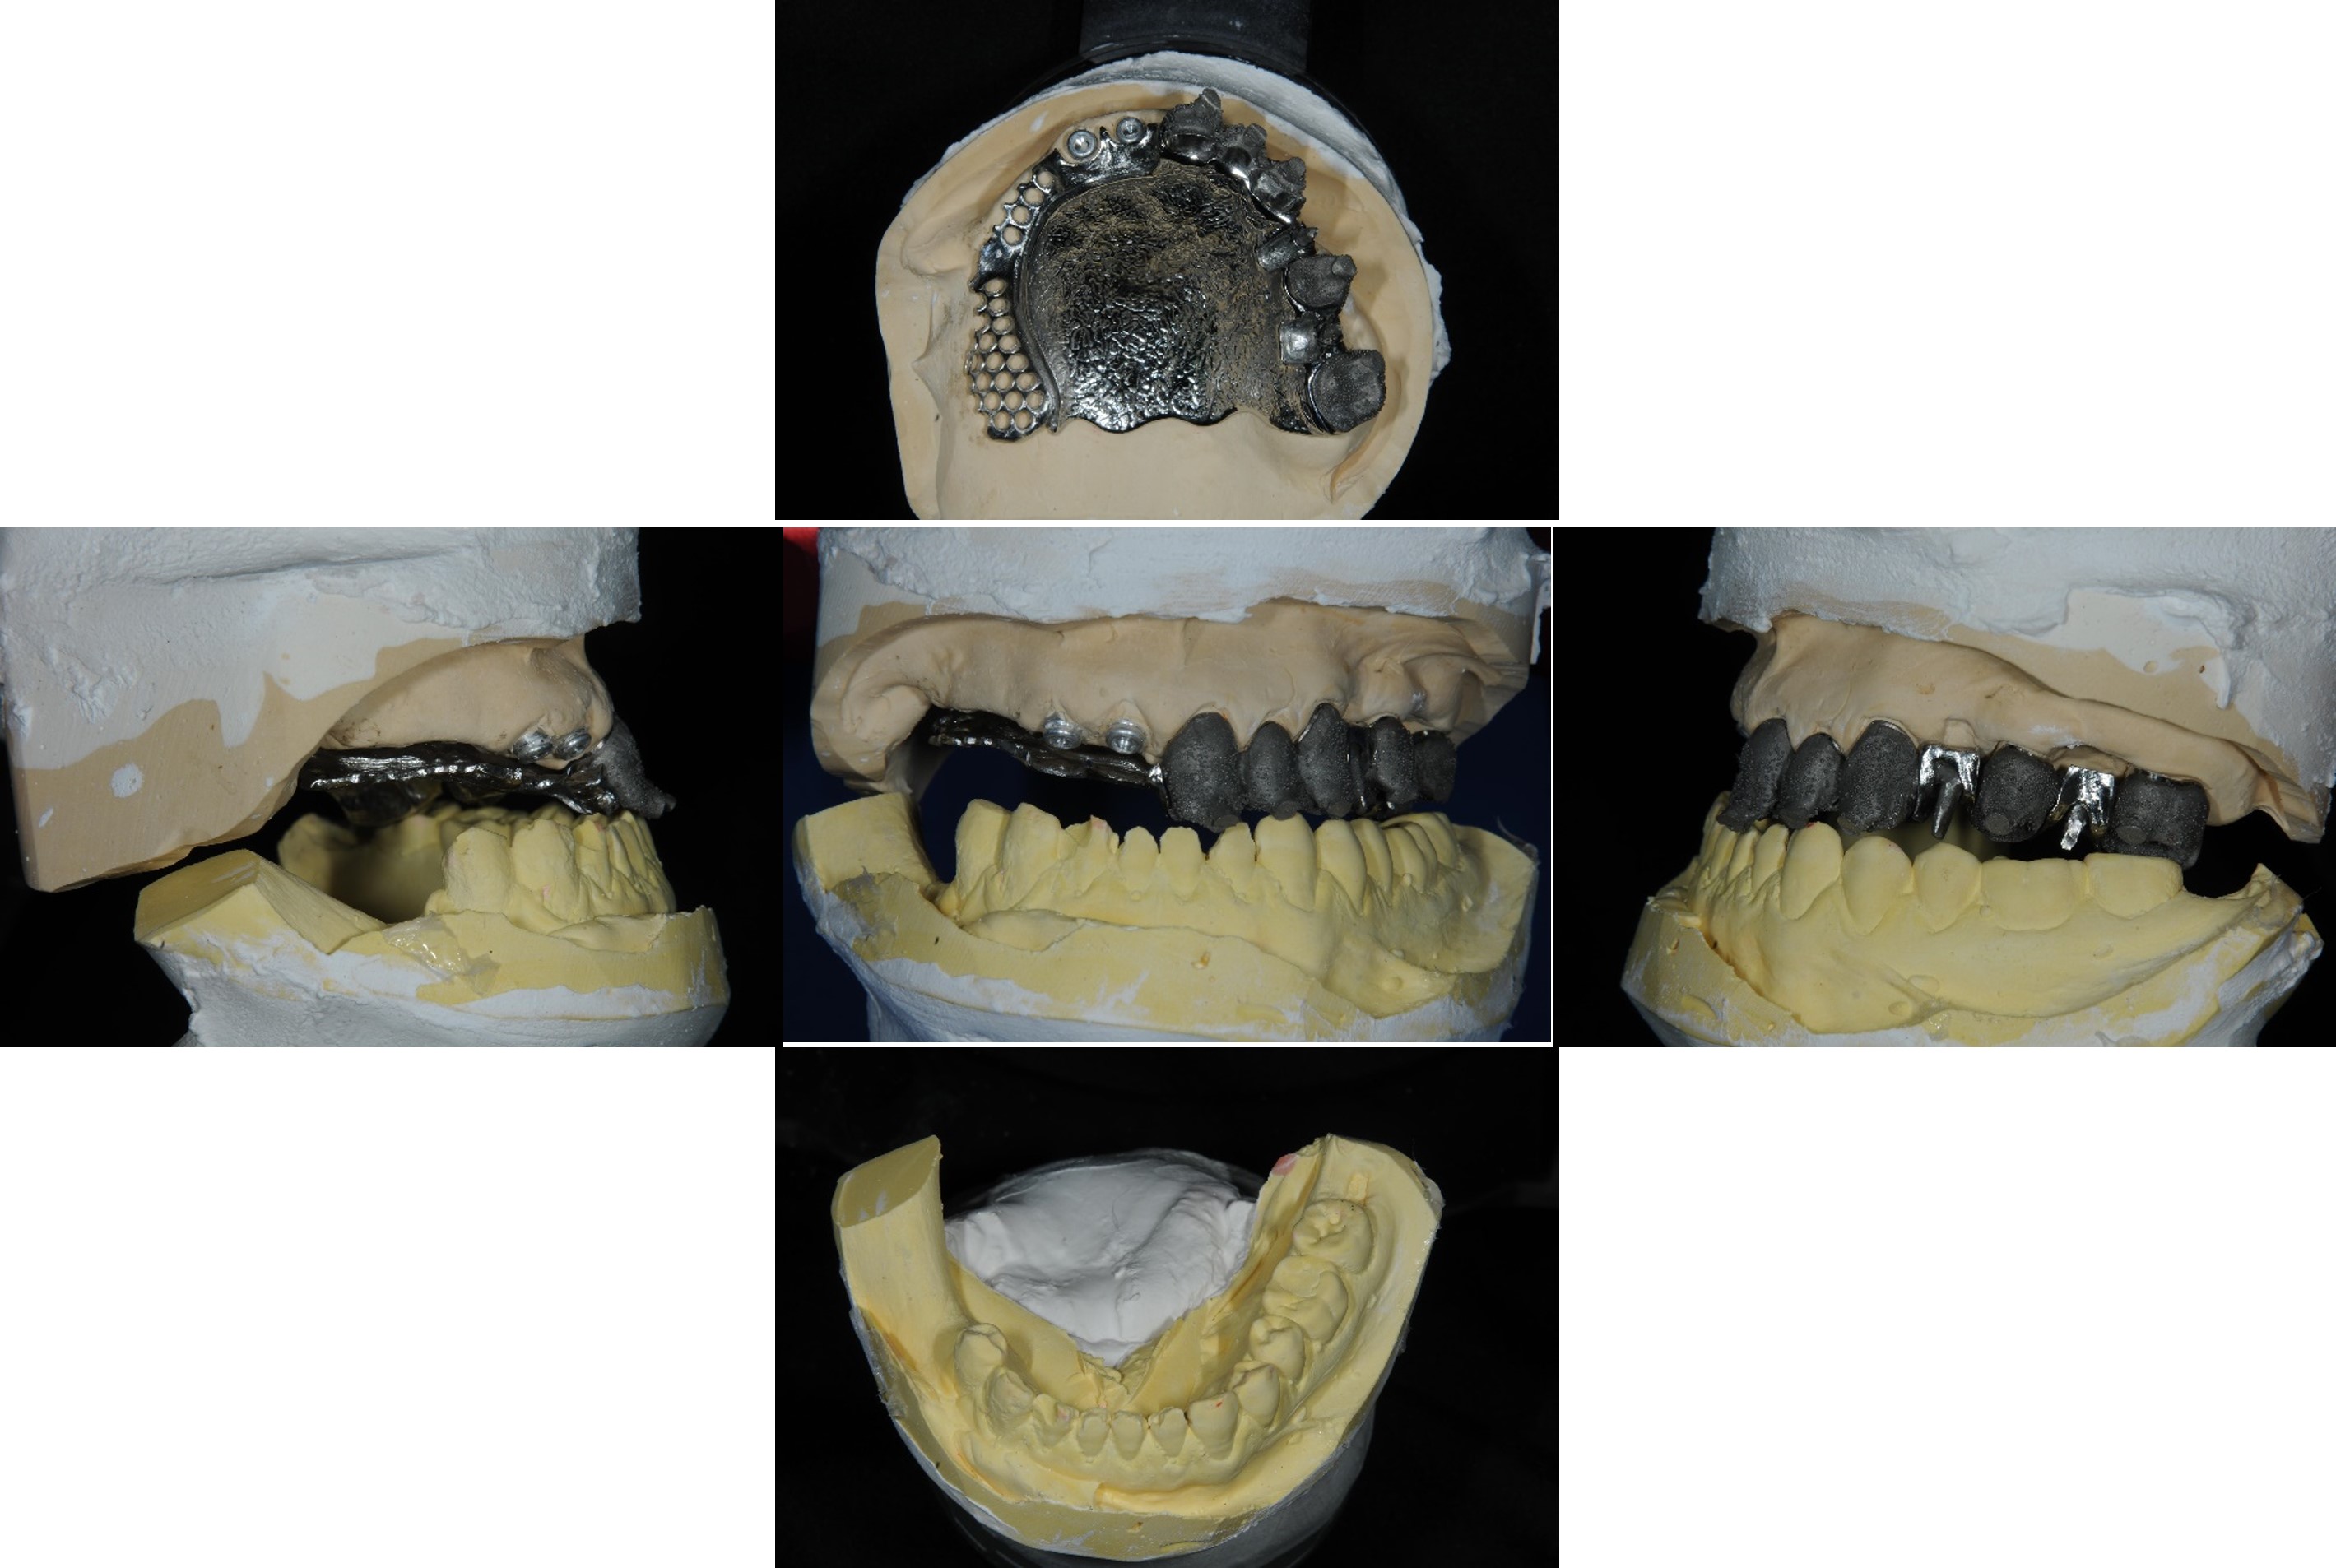

模型咬合分析

蠟型模擬最終可能成果

內冠套件

組合後外冠及活假牙套件

外冠及活動假牙套件

活動假牙套件